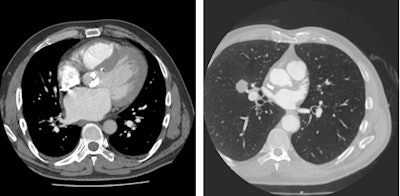

Delegates attending today's session will hear from experts how the cross-over in presentation between cardiac and pulmonary problems and their shared risk factors has led to growing demand for comprehensive cardiothoracic imaging for cardiopulmonary patients. Given the close interrelation of the lung and the heart, radiologists must always take a close look at the heart when assessing the lung and vice versa, say cardiothoracic imaging experts. This requires multiple reconstruction methods to visualize the whole chest cavity and dedicated focused areas of interest, plus an eye for alternative findings.

"In an aging population, it would be a mistake to only look at the lung aspects of a chest CT and ignore the cardiac aspects. The reverse is also true: cardiologists may ignore the noncardiac portion of a cardiac CT angiogram," said van Beek. "Lung cancer screening may show significant coronary calcifications, a direct predictor of a likely cardiovascular event over a five-year period. Similarly, lung cancer or emphysema may be revealed from cardiac studies; however, if you don't reconstruct the full field-of-view, these diseases will be easily missed."

ECR 2016 delegates will also be reminded of the subtle information available on CT and MR such as abnormal shape (D-shaping) of the interventricular septum, which may indicate pulmonary pressure overload or how thickened interlobular septae and pulmonary ground-glass opacities on CT may point to pulmonary congestion secondary to heart failure.